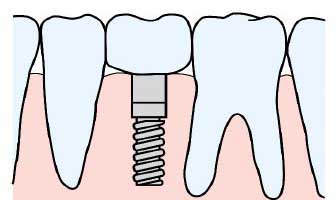

一本のインプラントを入れることで天然の歯と同じように噛むことができます

アバットメントに被さる人工歯冠を作製し、装着します